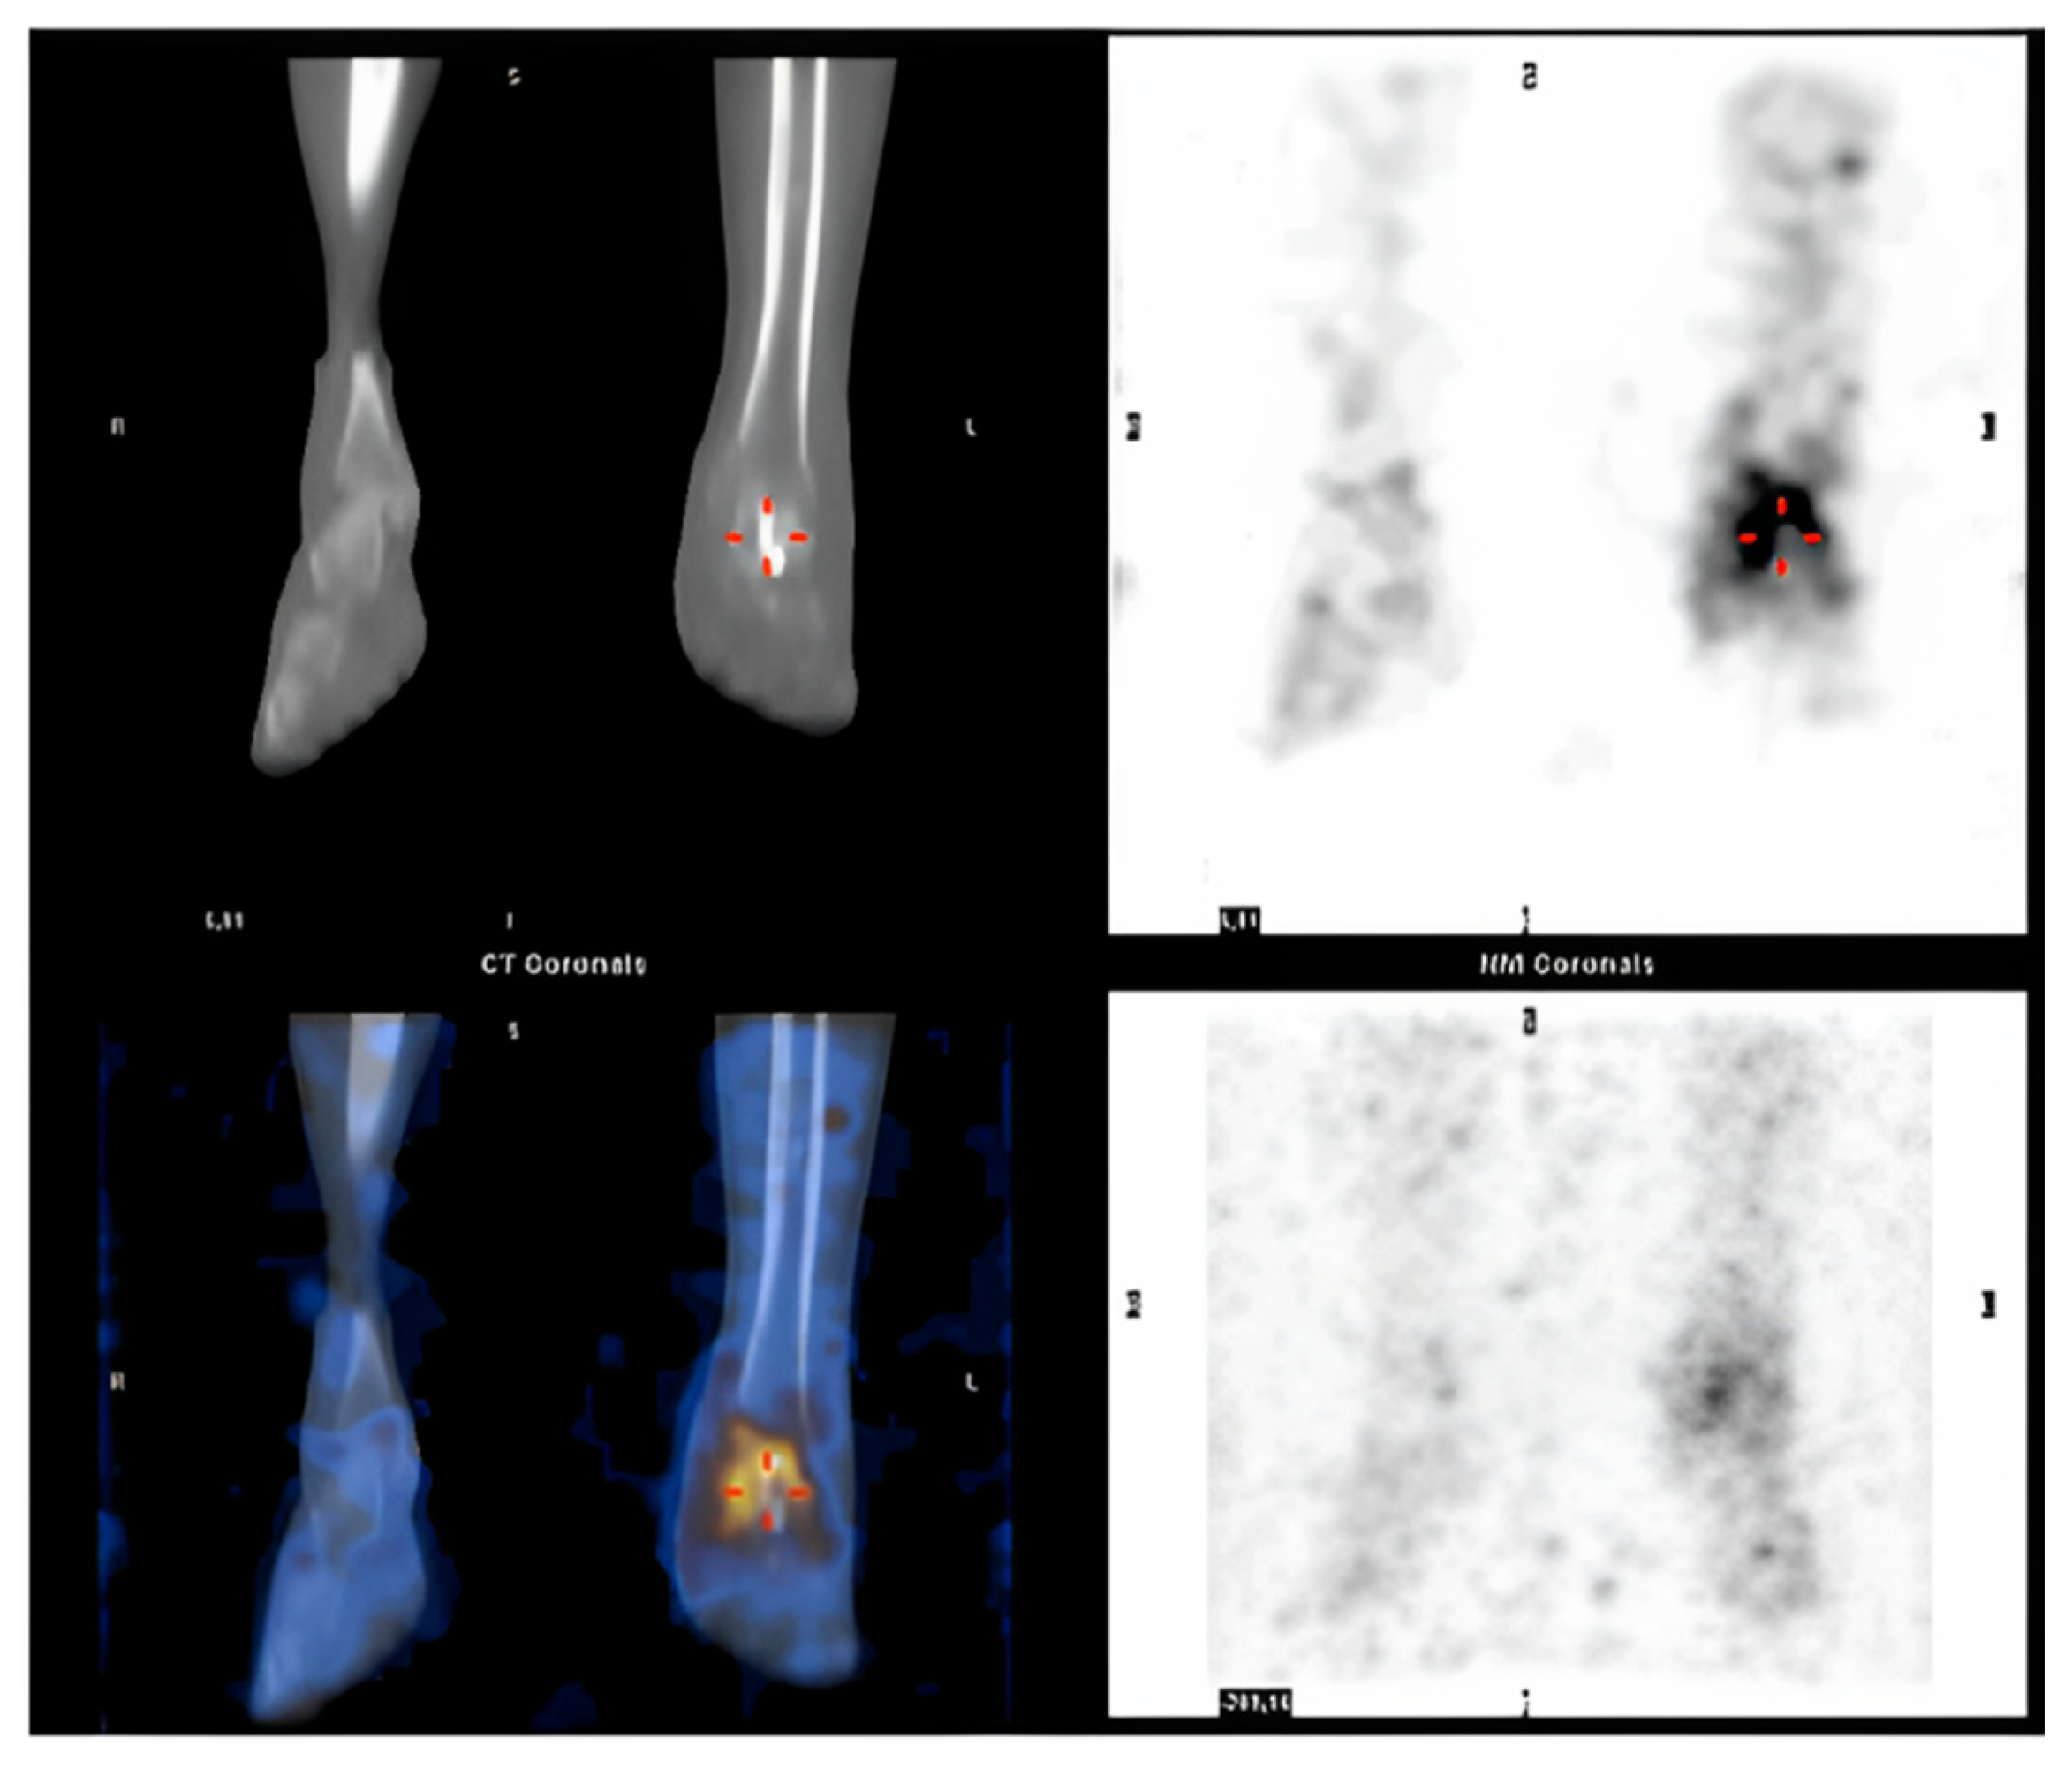

Post-operative recovery was uneventful. After two months, the patient started to complain of ankle pain and swelling: Single-photon emission computed tomography (SPECT-CT) confirmed the clinical suspicion of a deep tissue infection involving the reimplanted talus (Figure 3). The talus was removed and replaced by a new spacer in antibiotic-coated cement. A negative pressure treatment was applied to facilitate soft tissue healing.

Figure 3.

SPECT CT suggesting a deep tissue infection of the reimplanted talus. Red hyphens point out the site of infection.